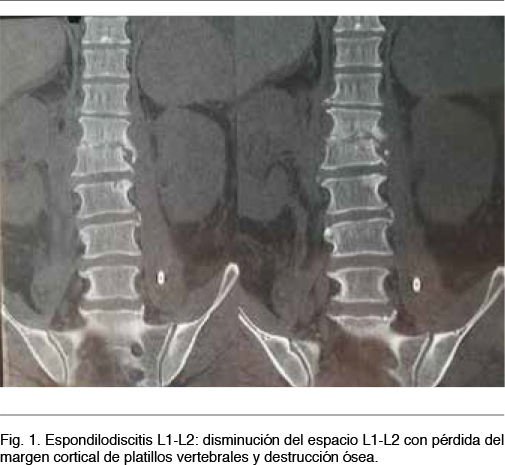

Se planteó diagnóstico de sepsis a punto de partida de espondilodiscitis piógena, con probable colección abdómino-pelviana. Se realizó TC de columna toraco-lumbo-sacra que confirmó el planteo de espondilodiscitis L1-L2, complicada con abscesos múltiples del psoas (Figuras 1 y 2).